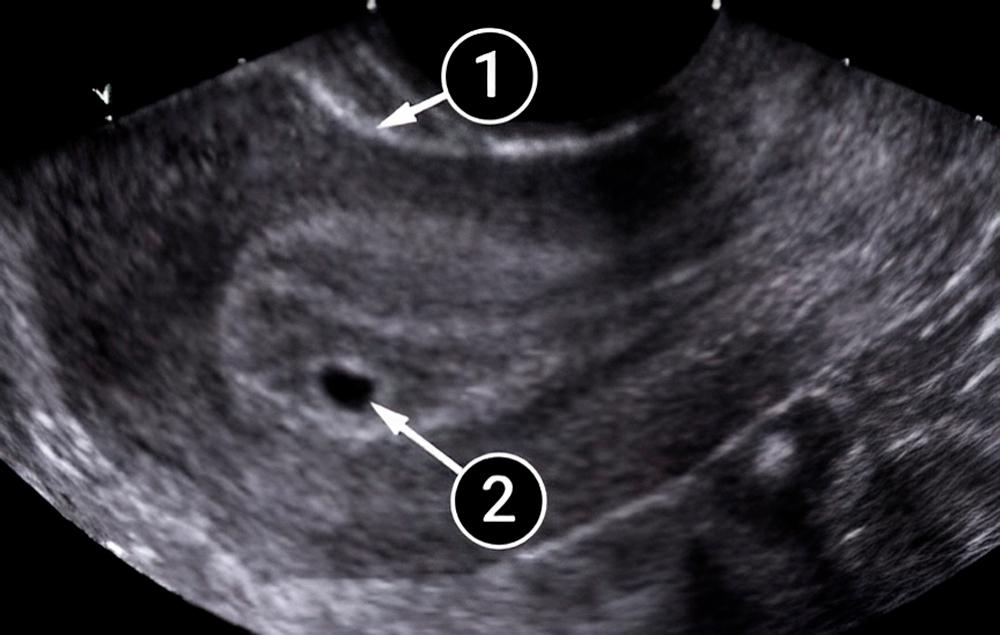

Lo que podemos ver en un ultrasonido

En la imagen inferior, se observa claramente el útero redondeado. En su interior se puede ver el saco amniótico rodeado por el endometrio. El saco amniótico es el óvalo oscuro con contornos claros ubicado en la parte inferior del útero, que se considera una de las posiciones más óptimas para el saco.

En la etapa actual del embarazo, el saco amniótico es todavía muy pequeño, sólo mide entre cinco y siete milímetros.